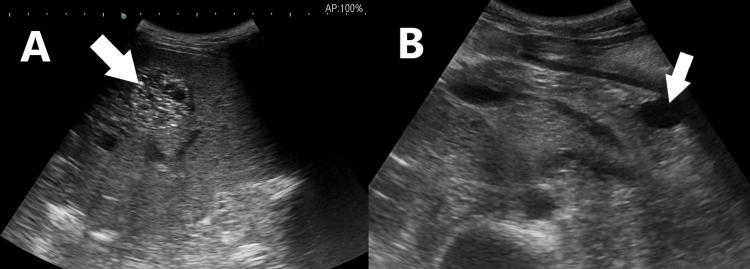

Growing teratoma syndrome (GTS) represents a rare yet significant complication following treatment for non-seminomatous germ cell tumors (NSGCT), characterized by the growth of mature teratoma elements despite prior chemotherapy. We present the case of a 30-year-old male who, following orchidectomy for NSGCT and subsequent chemotherapy, developed acute abdominal pain and pulmonary metastasis. Despite normal serum tumor markers, imaging revealed a large retroperitoneal mass encasing significant vessels. Surgical excision led to symptom resolution. This case underscores the diagnostic challenges GTS poses, the importance of imaging in diagnosis, and the efficacy of prompt surgical intervention in achieving favorable outcomes.

成熟性畸胎瘤综合征(GTS)是非精原细胞性生殖细胞肿瘤(NSGCT)治疗后一种罕见但严重的并发症,其特征是尽管先前进行了化疗,但仍有成熟畸胎瘤成分生长。我们报告了一例30岁男性病例,该患者因NSGCT接受睾丸切除术后并进行了后续化疗,出现了急性腹痛和肺转移。尽管血清肿瘤标志物正常,但影像学检查显示一个巨大的腹膜后肿块包绕了重要血管。手术切除后症状得以缓解。该病例强调了GTS带来的诊断挑战、影像学在诊断中的重要性以及及时手术干预在取得良好预后方面的有效性。